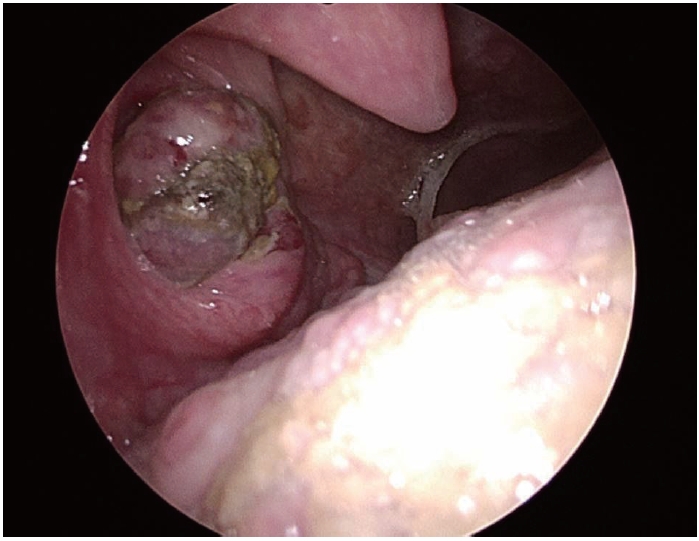

492 흡수성 판의 잔여물: 지속적인 비첨 감염 및 변형의 드문 원인

진홍률, 김수진

Korean J Otorhinolaryngol-Head Neck Surg. 2025;68(11):492-496.   Published online February 13, 2025

DOI: https://doi.org/10.3342/kjorl-hns.2024.00507

Cited By 1

kjorl-hns-2024-00507f1.jpgkjorl-hns-2024-00507f2.jpgkjorl-hns-2024-00507f3.jpgkjorl-hns-2024-00507f4.jpgkjorl-hns-2024-00507f5.jpg